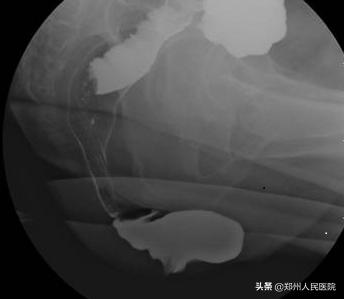

肛肠外科副主任张胜威了解情况后,他怀疑杨大妈患的不是普通的便秘。通过肛门指诊和直肠排粪造影,确定了杨大妈患的是 直肠前突型便秘 。经过 便秘MDT诊疗团队 会诊,由妇科和肛肠外科同时为杨大妈进行了阴道后壁修补术和直肠前突修补术,一次解决了两个问题。

咱们说的 直肠前突型便秘 ,作为出口梗阻型便秘的一种,又称直肠前膨出,多发生于中老年女性。 直肠前突 即直肠前壁突出,是直肠阴道隔薄弱直肠前壁突入阴道内的一种病理状态,是排便困难的主要因素之一。咱先来看看直肠的正常状态

再看看这个

这突出的地方像不像个鹅头这种影像学改变在临床上我们称之为 “鹅颈征” 是直肠前突型便秘的典型症状

妈呀看到这些小编不禁汗毛竖立如果您有这些症状,下一步就要来检查了 一般来说,医生在详细问询病史后,通常至少要做2个检查才能进一步确诊, 肛门指诊 和 排粪造影 。